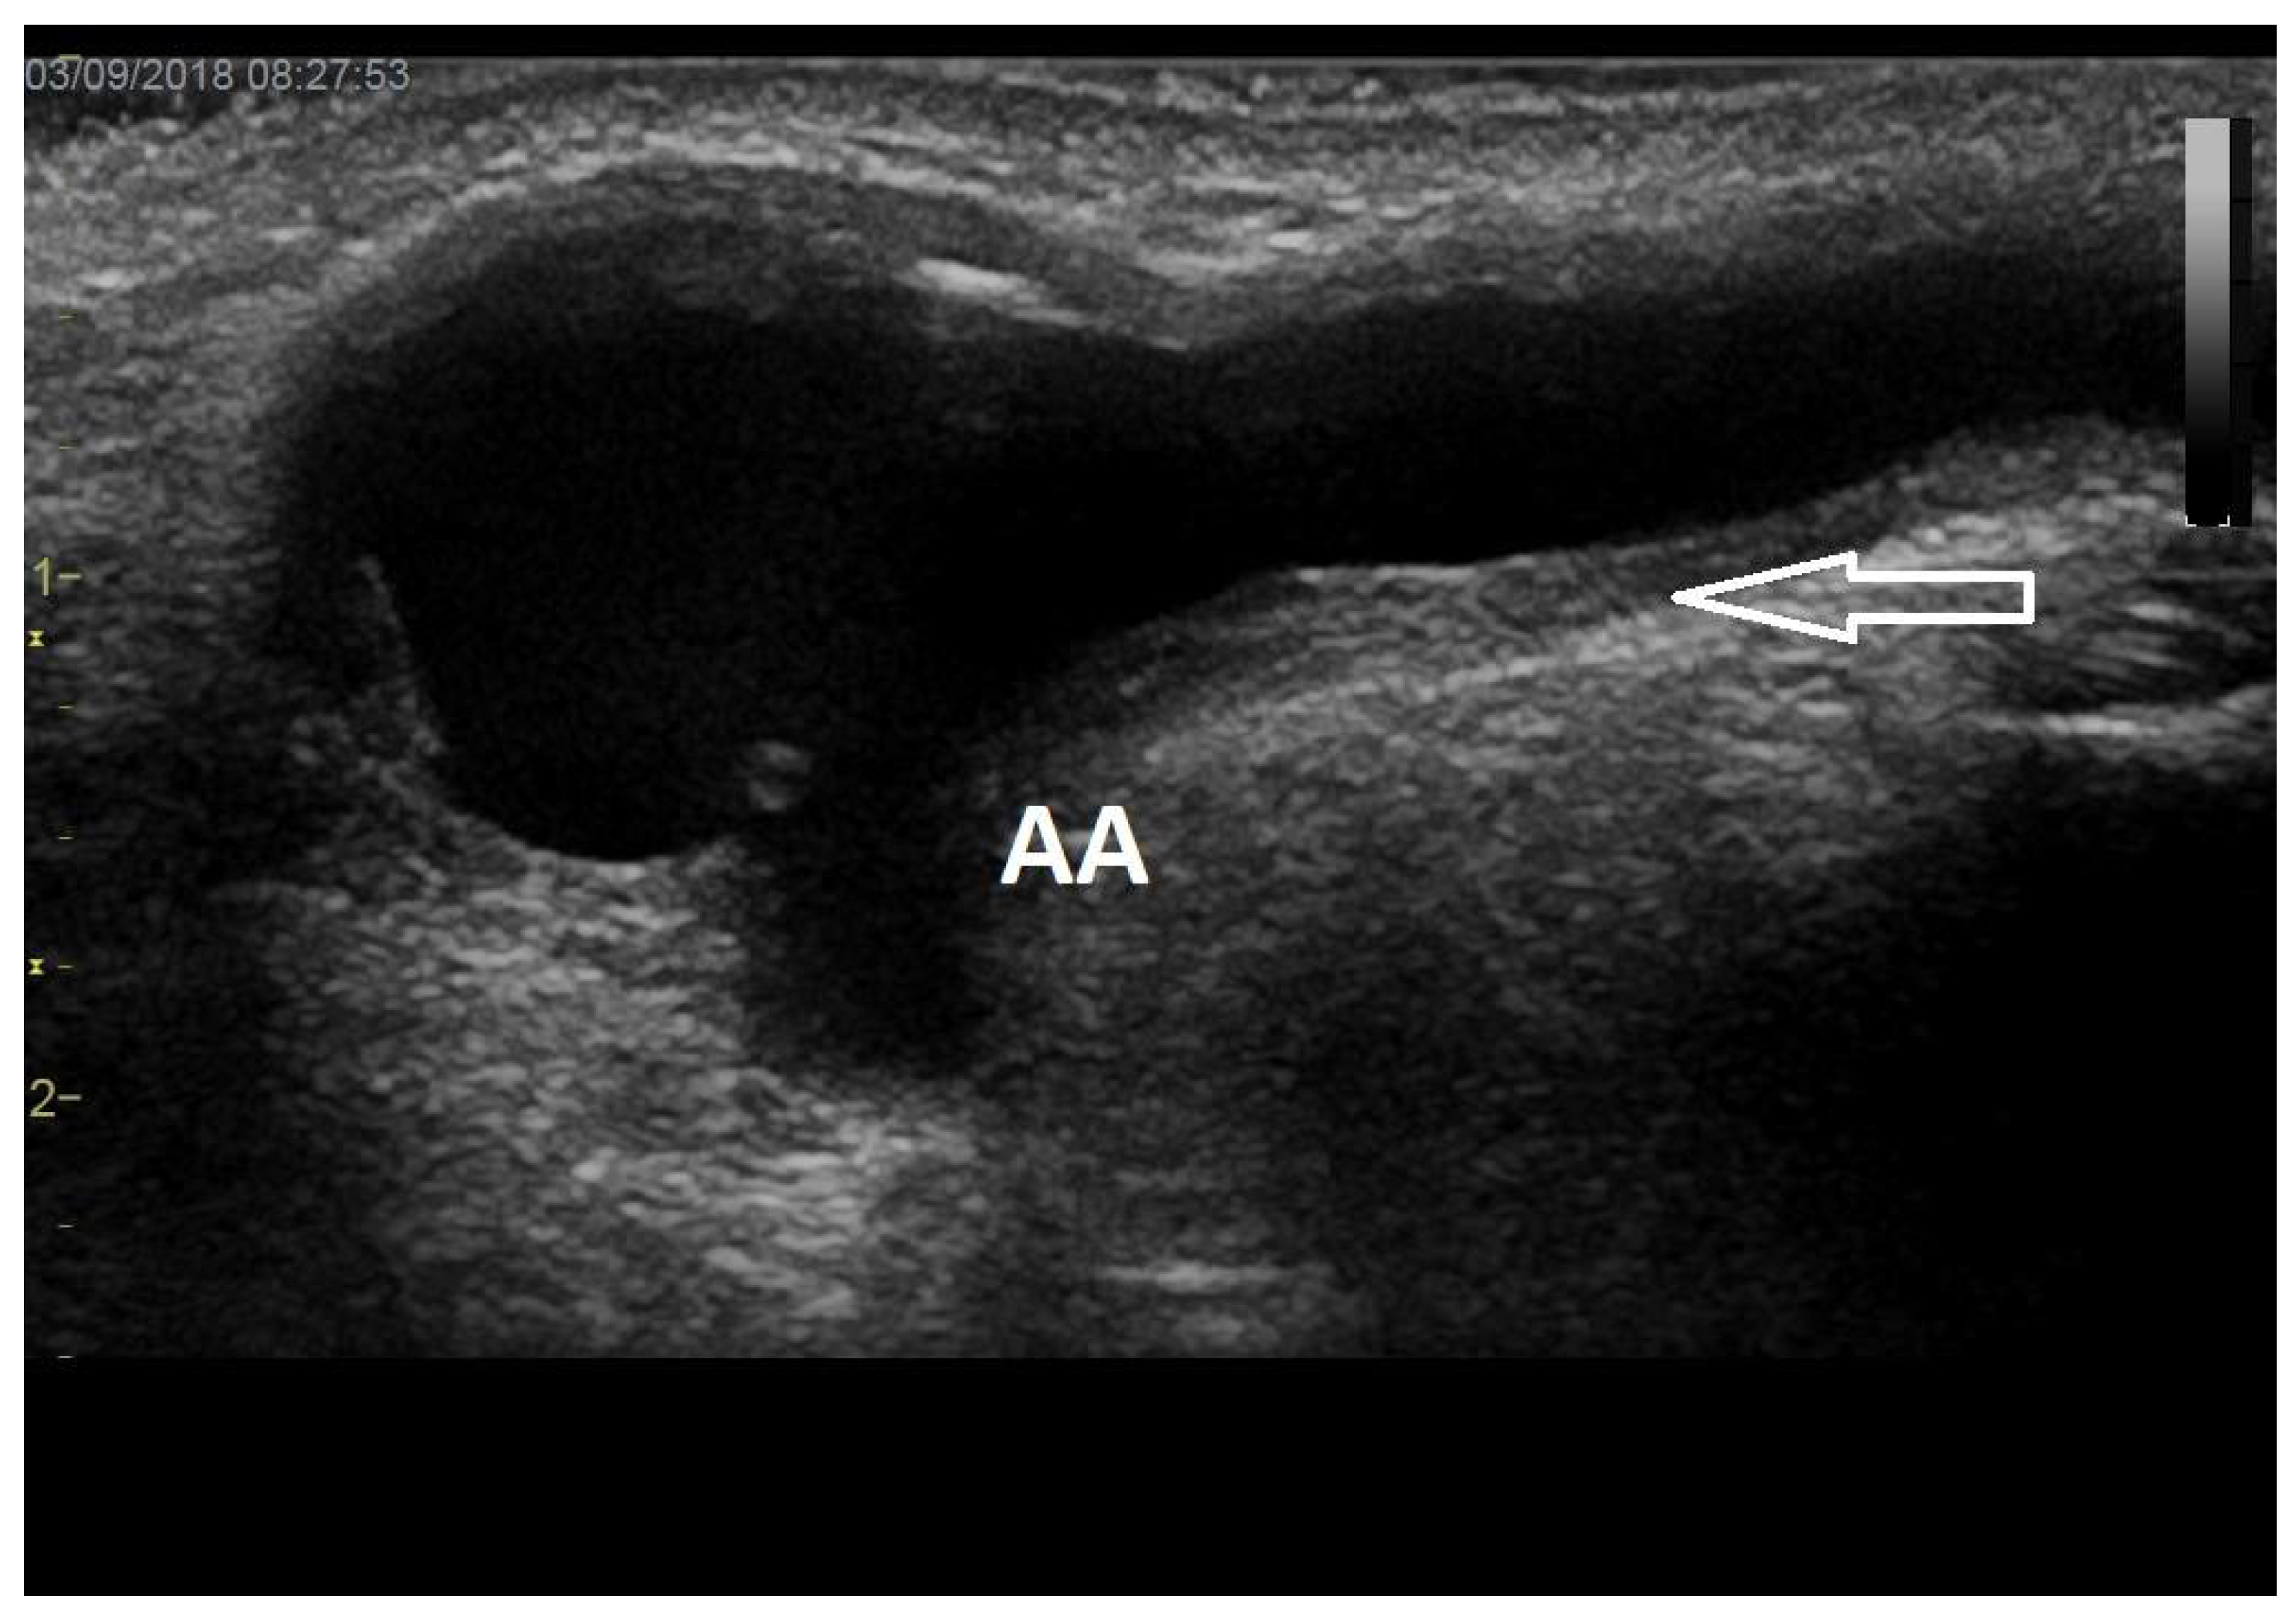

4. Predilectional Sites of Stenoses